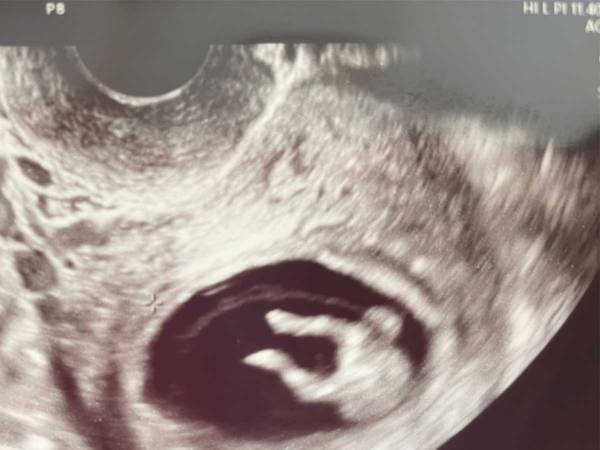

「足かわいすぎて、診察室の中、全員で笑った」

そんなコメントとともに、Twitterに公開された1枚の超音波写真をご紹介します。

人々が爆笑した理由が、ひと目で分かる、こちらの写真をご覧ください!

赤ちゃんの写真に、診察室にいた全員が爆笑! その理由がコチラです

ズコー!

なんと写真には、両足を宙へ放り出しているような、赤ちゃんの姿が写っていたのです!

まるでズッコケているかのように見える貴重な光景に、笑いがこみ上げます。